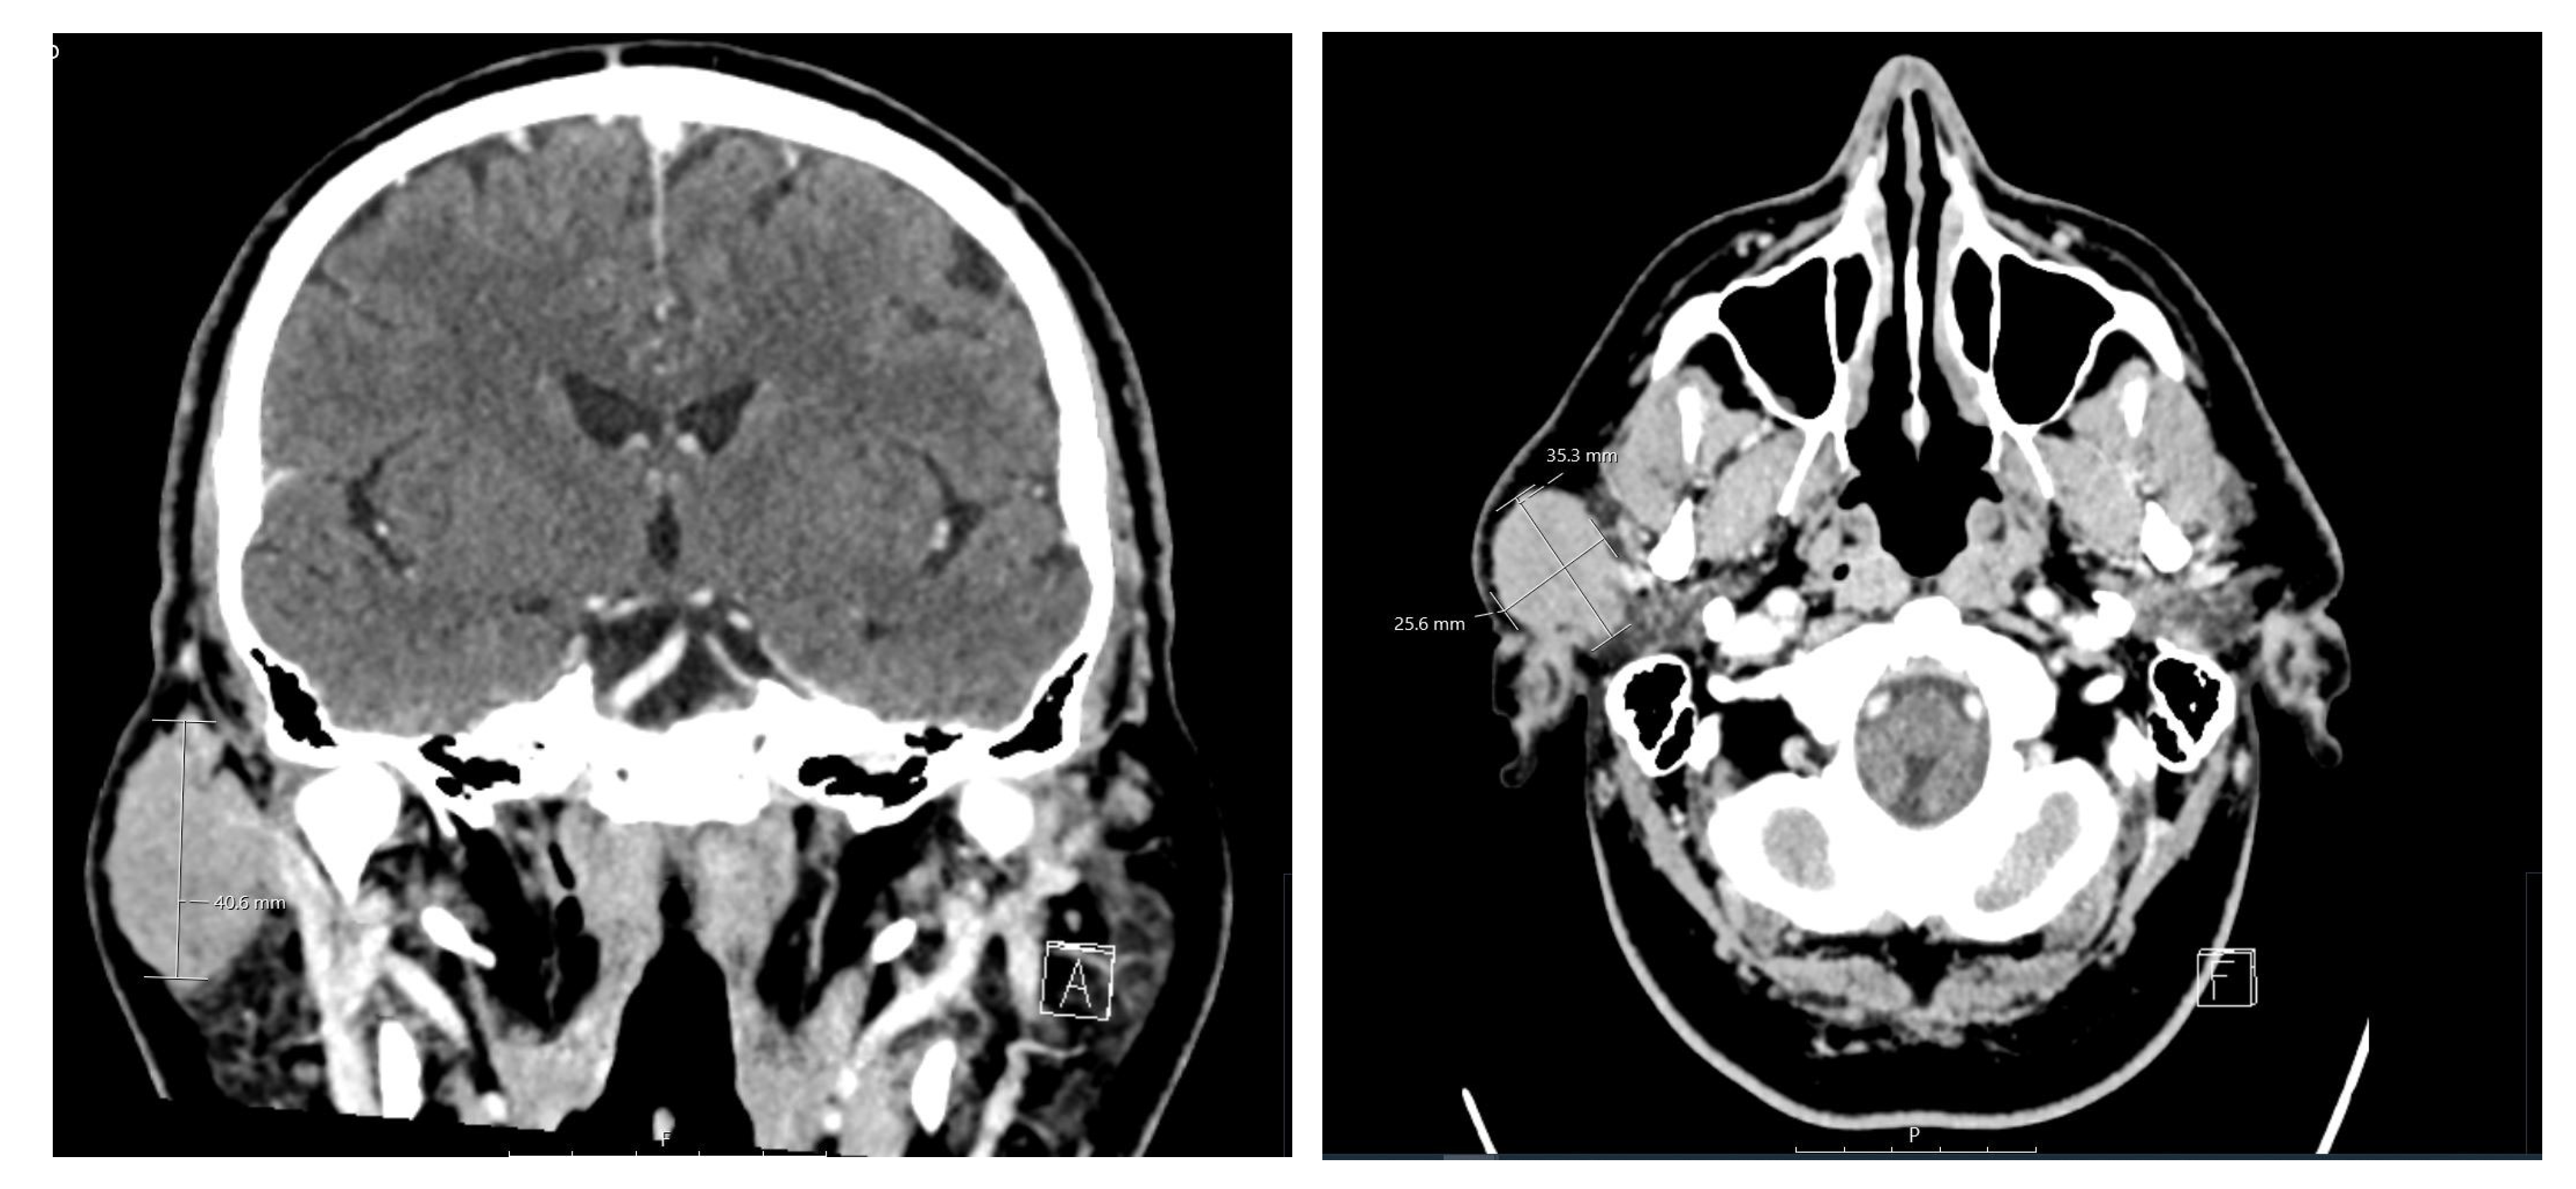

| Current case | 64 | M | Right parotid | WT | Follicular lymphoma/grade 1–2 |